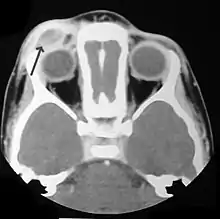

التشخيص

تأكيد التشخيص يتم نسيجيا عن طريق الخزع النسيجية،صبغة الهيماتوكسيلين والإيوسين ستوضح صفات خلايا لانجر هانز .

وجود حبيبات بيربك في المجهر الإلكتروني والصفات المناعية الخليوية الكيميائية مثل CD1 بشكل موجب هو أكثر تحديدا.

في البداية تستعمل اختبارت الدم الاعتيادية مثل تعداد الدم الكامل واختبار وظائف الكبد ،U and E s, تحاليل العظام لتحديد مناطق انتشار المرض واستبعاد الأسباب الأخرى، الأشعة ستبين الأضرار في العظم ومدى الدمار في الرئة . قد تستعمل الأشعة السينية والمقطعية والرنين المغناطيسي واختبار وظائف الغدد الصماء وغيرها من أدوات التشخيص.